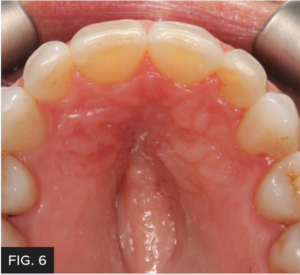

Photographs were taken to evaluate aesthetic outcome. The patient was shown her new restoration and was pleased with the results. The patient returned a few weeks later for a final post-op check. The tissue healed well after removal of the attachments. Proper canine function was confirmed and lateral disclusion of the lateral was obtained which is ideal with a Class IV restoration on such a small sized tooth.12 The final pictures2 and post-op x-rays were taken. (FIG 8 & 9)

The missing incisal third of this patient’s tooth was successfully restored with an easy-to-handle nanofill composite with superior blending qualities. The addition of tiny craze lines helped make the restoration even more undetectable and the transparent microfill surface ensured perfect polishability. Treatment was completed in one appointment and no touchups were needed. The patient was comfortable during the treatment and extremely pleased with the result. The best composite restoration is one that cannot be detected, because everything looks like natural tooth structure.